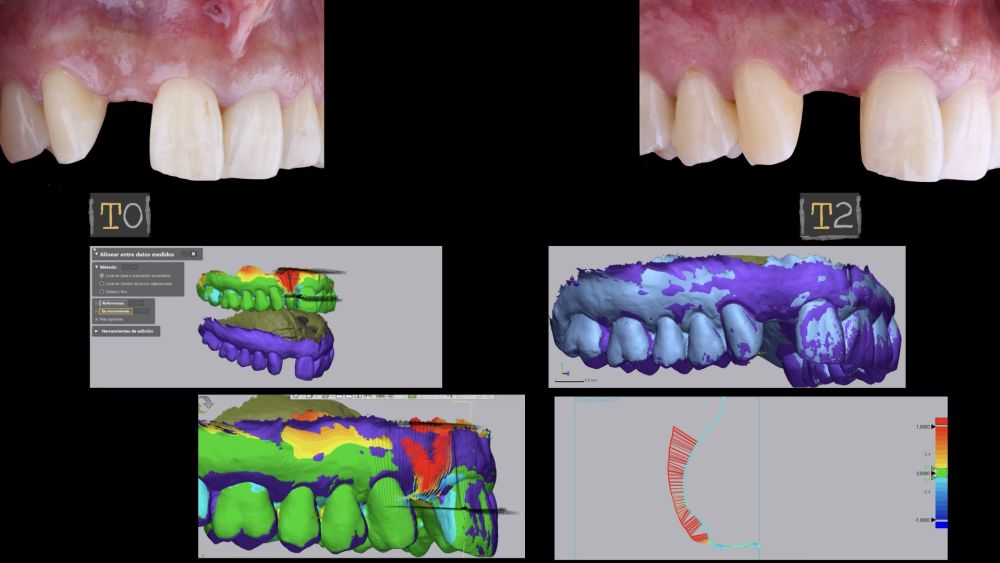

1.3 Mediciones digitales del tejido blando vestibular aumentado

El sitio donde se realizó la cirugía (implante 1.2), junto a su arco completo, se escanearon utilizando un escáner óptico intraoral en diferentes periodos de tiempo; tres semanas antes de la cirugía (T0), inmediatamente después de la cirugía (T1) y al mes y medio tras la cirugía (T2). Los modelos digitales generados se exportaron y guardaron como archivos STL para posteriormente importarlos al software de análisis de imágenes (Geomagic® Control X™; 3D Systems, Rockhill, SC). Se realizó el análisis de los cambios de espesor preoperatorios (T0) frente a los postoperatorios (T1 y T2). Estos cambios de espesor longitudinales se analizaron en la cara vestibular de la corona implantosoportada con la función “3D Compare”, lo que permitió crear un mapa de colores tras la superposición de los modelos, para analizar cuantitativamente las variaciones ocurridas en las áreas de intervención. El mapa de colores oscila entre +3 mm hasta -3 mm, con una tolerancia de ± 0,15 mm y se interpreta de la siguiente manera: áreas verdes corresponden a un alineamiento perfecto de los modelos; los colores rojos, naranjas y amarillos se interpretan como una ganancia de volumen y los colores azul oscuro y claro representan respectivamente una pérdida volumétrica (Figuras 8 y 9). Posteriormente, se diseñó una región de interés rectangular para el estudio del área de intervención donde se evaluaron los cambios lineales de la mucosa periimplantaria (Figuras 8 y 9). La extensión horizontal de la región de interés abarcó ambas papilas (mesial y distal) cubriendo el contorno marginal de la corona implantaría hasta la superficie marginal de los dientes adyacentes. Para informar los resultados de interés, se identificaron puntos en el plano horizontal previamente diseñado en la cara vestibular del implante, comenzando desde mesial y extendiéndose 0,5 mm de distancia en dirección distal. Los valores positivos indicaron que los tejidos periimplantarios estaban ubicados más bucalmente (> grosor) mientras que los negativos denotaron que los tejidos periimplantarios estaban ubicados más a palatino (< grosor).

El resultado clínico final fue satisfactorio cumpliendo las demandas estéticas del paciente. Los tejidos blandos estaban morfológicamente y dimensionalmente estables sin ningún signo de inflamación. Sin embargo, los cambios del tejido blando periimplantario (espesor volumétrico vestibular) fueron demostrados de manera cualitativa y cuantitativa (Figuras 8 y 9). En el postoperatorio inmediato (T1), la ganancia media obtenida al comparar T0 frente a T1 fue de 0,88 ± 0,15 mm con un incremento máximo de 1,1 mm. Al comparar T0–T2, se observó una ganancia media de 0,73 ± 0,23 mm. Es decir, se ha producido una contracción de volumen de 0,16 mm desde la colocación del injerto (T1) hasta pasado un mes y medio (T2).